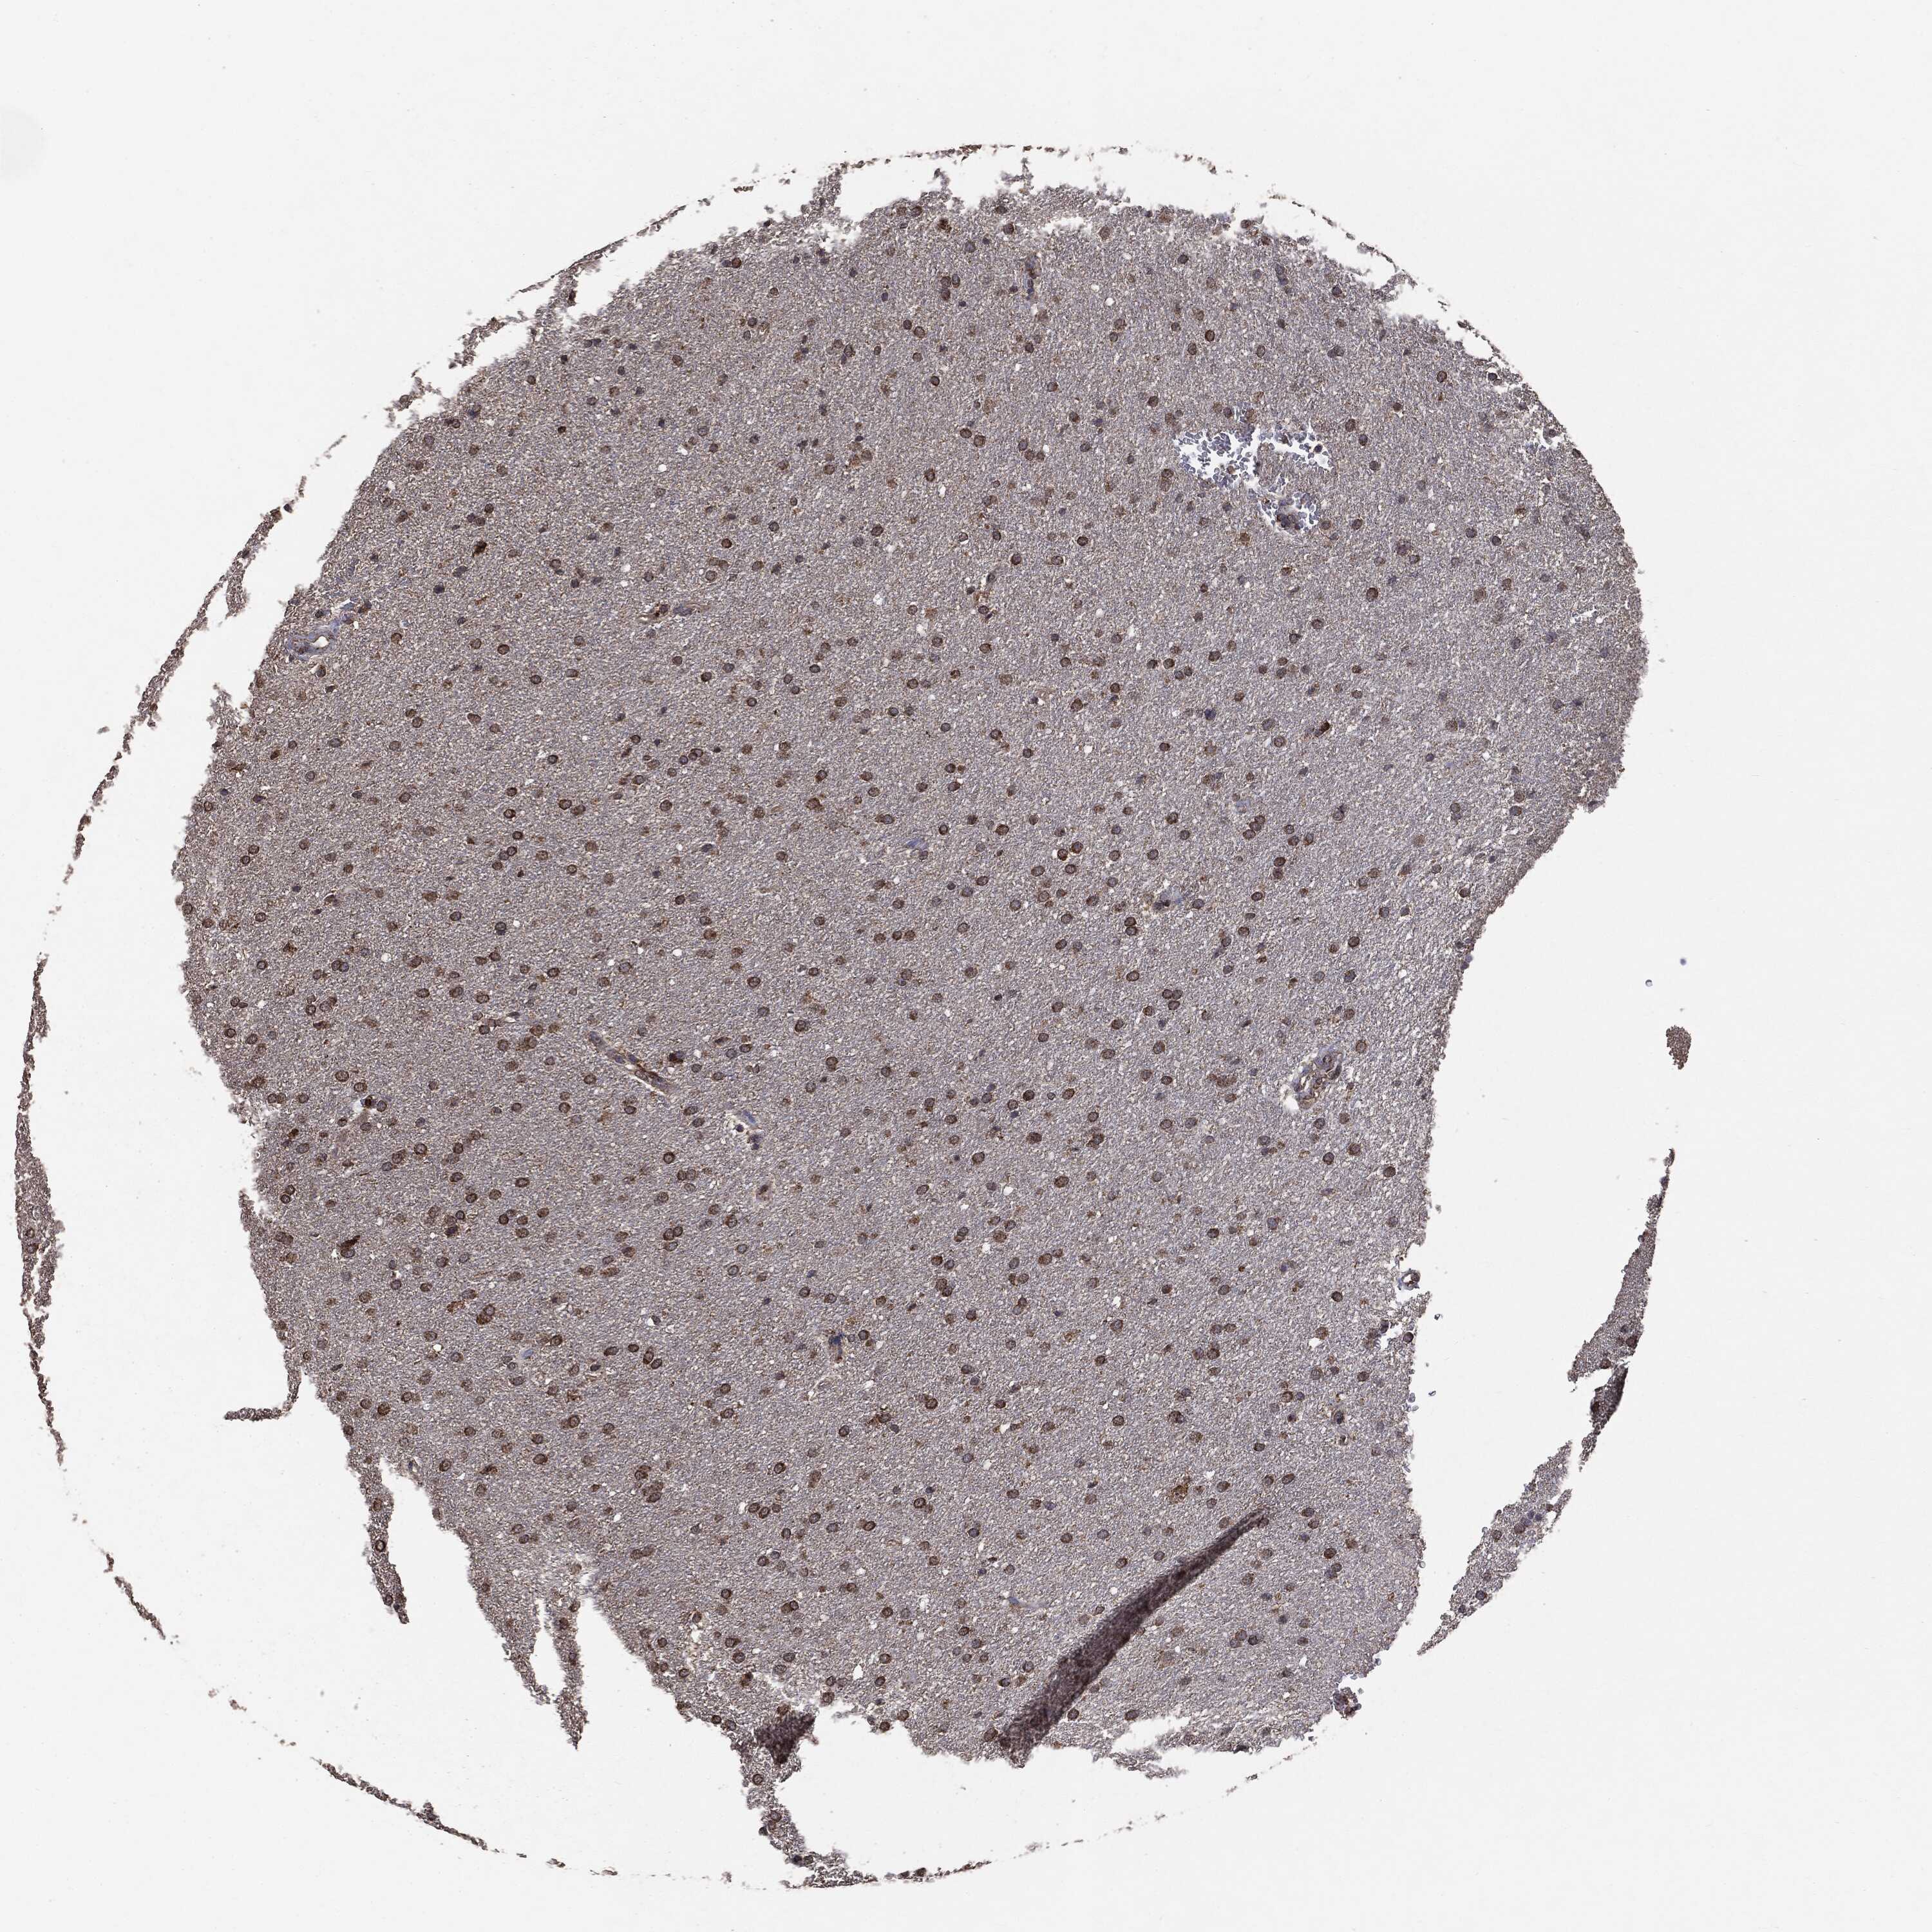

GLIOMA - Protein expressioni

A mouse-over function shows sample information and annotation data. Click on an image to view it in a full screen mode. Samples can be filtered based on level of antibody staining by selecting one or several of the following categories: high, medium, low and not detected. The assay and annotation is described here.

Note that samples used for immunohistochemistry by the Human Protein Atlas do not correspond to samples in the TCGA dataset.

Antibody stainingi

Antibody staining in the annotated cell types in the current human tissue is reported as not detected, low, medium, or high, based on conventional immunohistochemistry profiling in selected tissues. This score is based on the combination of the staining intensity and fraction of stained cells.

Each image is clickable and will lead to virtual microscopy that enables deeper exploration of all samples and also displays staining intensity scores, fraction scores and subcellular localization as well as patient and tissue information for each sample.

CAB069425

CAB080053

CAB080065

CAB080070

CAB080081

CAB080095

CAB080097

Staining

High

Medium

Low

Not detected

Intensity

Strong

Moderate

Weak

Negative

Quantity

>75%

75%-25%

<25%

None

Location

Nuclear

Cytoplasmic/membranous

Cytoplasmic/membranous,nuclear

Glioma, malignant, Low grade

Glioma, malignant, High grade

Glioma, malignant, NOS